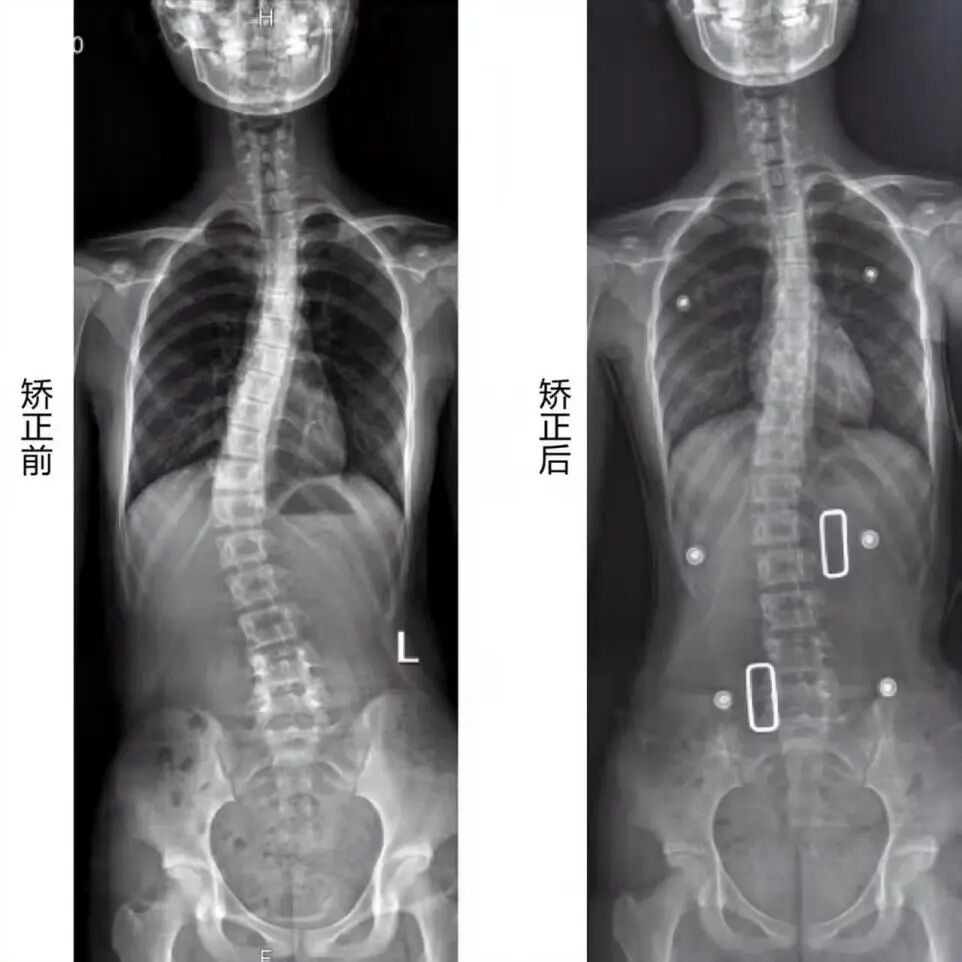

中国医学装备协会放射影像装备专委会常务委员郭亮教授通过“从负重锥束CT到全身骨骼三维诊疗系统诊治深度融合的迈进”分享了负重锥束CT的技术原理与临床应用价值。该系统实现了站立位下全身低剂量三维成像,并融合AI算法自动精准提取近200项三维参数,有效避免了传统二维影像因体位与投照角度引起的误差,可真实呈现负重状态下骨关节的结构与力学状态,在脊柱侧弯评估、关节退变诊断、手术规划及3D打印个性化导板与支具等方面具有突出价值,推动了影像诊断从二维形态评估向三维生物力学精准诊疗的跨越。

山医大一院CT放射影像科现配备三维骨关节与AI测量负重锥束CT及岛津SONIALVISION C200高端设备,可实现脊柱、关节的负重锥束CT三维AI精准测量,以及全身关节动态功能评估、负重位断层摄影等多项特色检查,截至目前,科室累计完成青少年负重锥束 CT 三维测量177例,为临床诊疗提供精准量化数据支撑,实现个性化支具定制与适配佩戴,从而达成高效的矫形矫正效果。诚邀各临床科室莅临参观交流、实践合作,协作挖掘负重锥束CT三维AI精准测量在骨关节领域的价值,共同携手为患者制定更精准化、个性化的诊疗方案,共促相关学科发展。